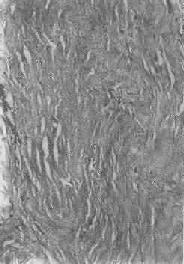

肝淀粉样变

图1-22 肝淀粉样变

淀粉样物质呈均质状,沉着于窦内皮下,肝细胞索受压萎缩